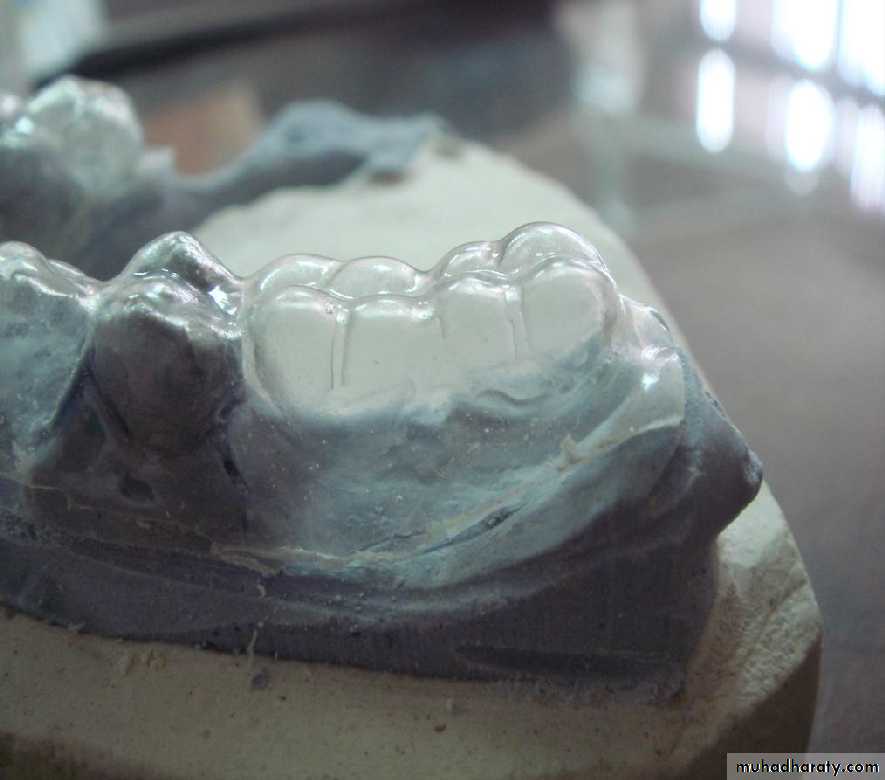

• coping• 2- Tooth reduction and cast coping of vital abutment

• B- Tooth reduction• and cast coping

• 2- Tooth reduction and cast coping of vital abutment

• Gold or metallic cast Copings and telescopic crowns are a method of improving overdenture retention. These

• may be conical crowns (semi- parallel wall) with a friction adaptation at the marginal area of the abutment, or Milled crowns for larger areas and parallel surfaces.

• Friction retention is more commonly used in exclusively tooth-supported overdentures

that are not supported by soft

tissue.